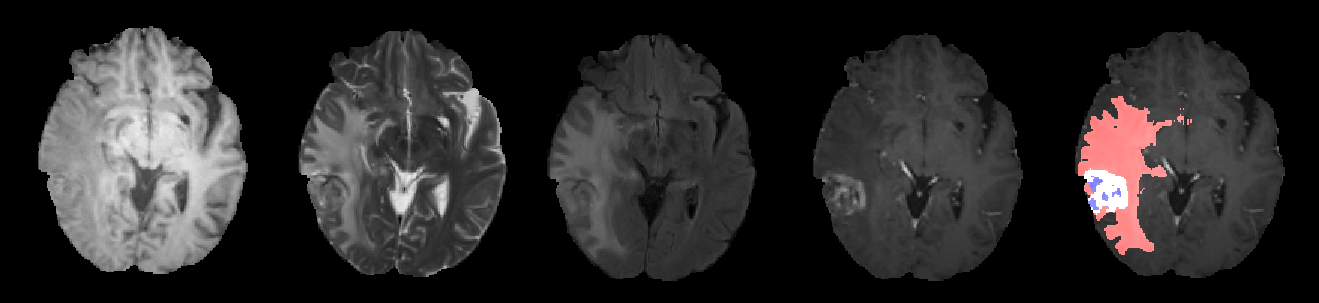

Brain gliomas can be well detected using magnetic resonance imaging. The whole tumor is visible in T2-FLAIR, the tumor core is visible in T2 and the enhancing tumor structures as well as the necrotic parts can be visualized using contrast enhanced T1 scans. An example is illustrated in figure 1.

We used the BRATS 2017 training and validation sets for our experiments [1, 2, 3, 4]. The training set contains 285 patients (210 high grade gliomas and 75 low grade gliomas). The BRATS 2017 validation set contains 46 patients with brain tumors of unknown grade with unknown ground truth segmentations. Each patient contains four modalities: T1, T1 with contrast enhancement, T2 and T2 FLAIR. The aim of this experiment is to segment automatically the tumor necrotic part, the tumor edema and the tumor enhancing part.

Due to our training data preparation (class wise segmentation smoothing) and due to our data augmentation method (additive noise), our segmentation results tends to be smoother than the ground truth segmentation. This effect is illustrated in figure 6.

Different segmentation results are illustrated in figure 7. The proposed network tends to produce smooth and compact segmentation results which are often very close in terms of Euclidean distance to the ground truth segmentation. We have consciously chosen to privilege this effect by smoothing the ground truth segmentation and augmenting data with additive noise. Different approaches may be better suited for other kind of quality metrics.